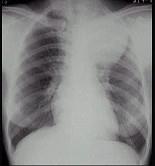

问题 女,25岁,胸背痛2周,胸片如图,最可能的诊断为 ( )

选项 A.左上肺不张 B.左上肺炎 C.纵隔肿瘤 D.左上肺癌 E.左上肺炎性假瘤

答案 C